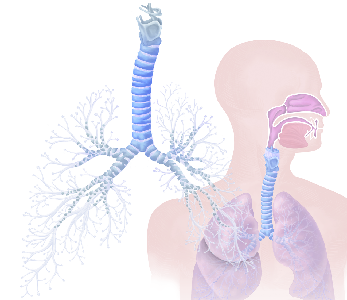

Detailreiche Fotografien aus der medizinischen Praxis ergänzen die Texte; moderne, genaue,

wissenschaftliche Zeichnungen geben Einblick in die Anatomie und die Funktion der Lunge und

anderer Organe.